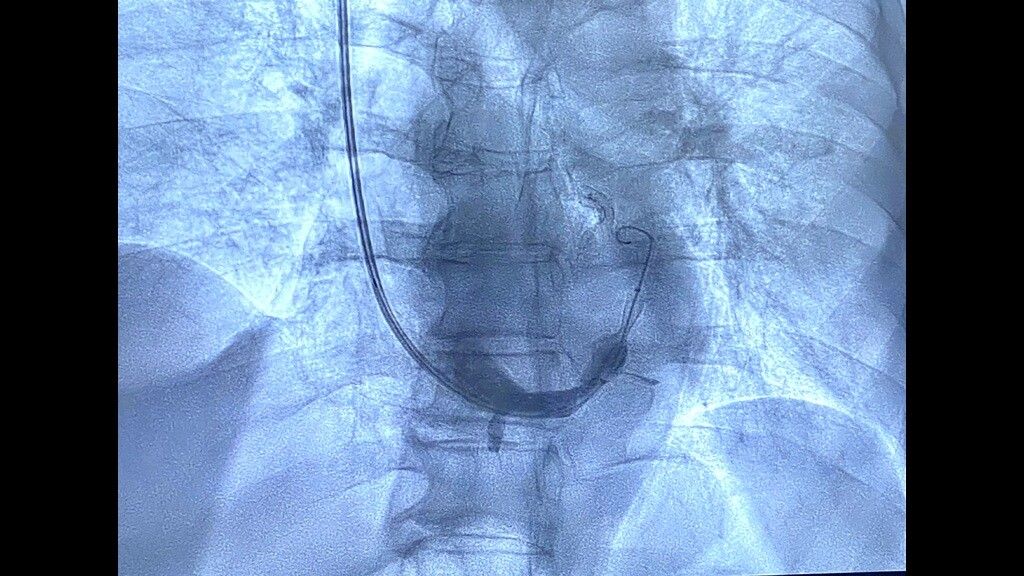

“Abbiamo eseguito questo intervento invasivo ma non chirurgico – ha spiegato Bonfantino - in un paziente di 63 anni, in anestesia locale, che è consistito nell’impianto di uno stent metallico (reducer), a forma di clessidra,  attraverso la vena giugulare, all’interno del seno coronarico, cioè la vena che sbocca nell’atrio destro del cuore e che drena tutto il sangue venoso di origine cardiaca, per poi raggiungere i polmoni ed essere ossigenato.  Questa procedura  - ha aggiunto -trova indicazione in quei pazienti coronaropatici sintomatici, che lamentano angina pectoris nonostante terapie farmacologiche ad alto dosaggio.  La presenza di tale sintomatologia, anche assumendo una terapia farmacologica ottimizzata, determina un aumentato rischio ischemico cardiaco e genera grande frustrazione per i pazienti che non sono quindi in grado di svolgere in serenità le normali attività quotidiane”.

L’impianto dello stent reducer in sala è stato coordinato dal dottor Maurizio Turturo, responsabile della UOS Emodinamica, e dal dottor Francesco Cassano. “Grazie alla particolare morfologia dello stent, a forma di clessidra – ha detto Turturo - si determina un rallentamento del drenaggio venoso cardiaco, permettendo la persistenza nel cuore di sangue ancora ossigenato e quindi il rilascio di una maggiore quantità di ossigeno al muscolo cardiaco. Ciò determina, in un’alta percentuale di casi, la risoluzione dei sintomi anginosi del paziente e il sensibile miglioramento della qualità di vita del paziente”.